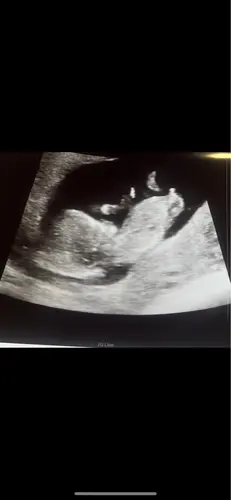

Iemand enig idee? De vk zei dat ze (maar totaal nog niet betrouwbaar) dacht dat het weer een jongetje zou worden😊 Ben nu precies 11 weken.

Vooralsnog zou ik zeggen een meisje😊 maar eigenlijk is het nog te vroeg lees ik overal, beste vanaf 12 weken omdat de hoek nog kan veranderen. Ik heb ook uit nieuwsgierigheid mijn echo foto in deze chat gestuurd met 11 weken haha!

Ik vind 'm te onduidelijk om af te lezen